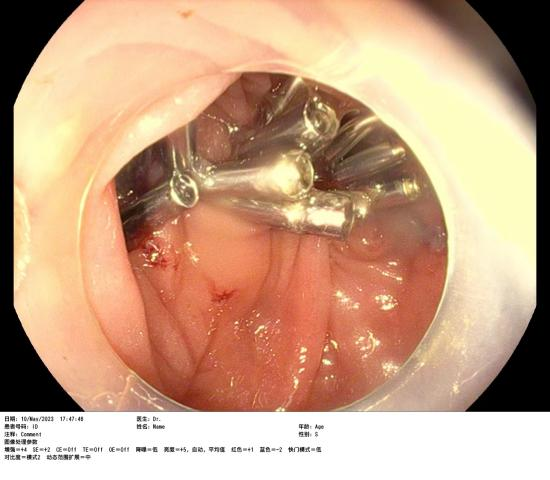

患者賴女士因下腹部疼痛不适半月,在惠州六院行腸鏡檢查時(shí)發(fā)現橫結腸腫物,腫物大小約2.8cmx2.0cm,表面(miàn)充血,于是入院完善采血、心電圖、胸片、全腹部增強CT等一系列檢查,增強CT結果提示腫物未見腸管外浸潤生長(cháng),經(jīng)評估該患者有手術指征,在與患者及家屬充分溝通後(hòu),由消化内科蘇連明副主任醫師爲患者行内鏡下結腸黏膜剝離術(ESD),手術非常順利,術後(hòu)病理及免疫組合明确診斷爲高級别上皮内瘤變——俗稱早期結腸癌。